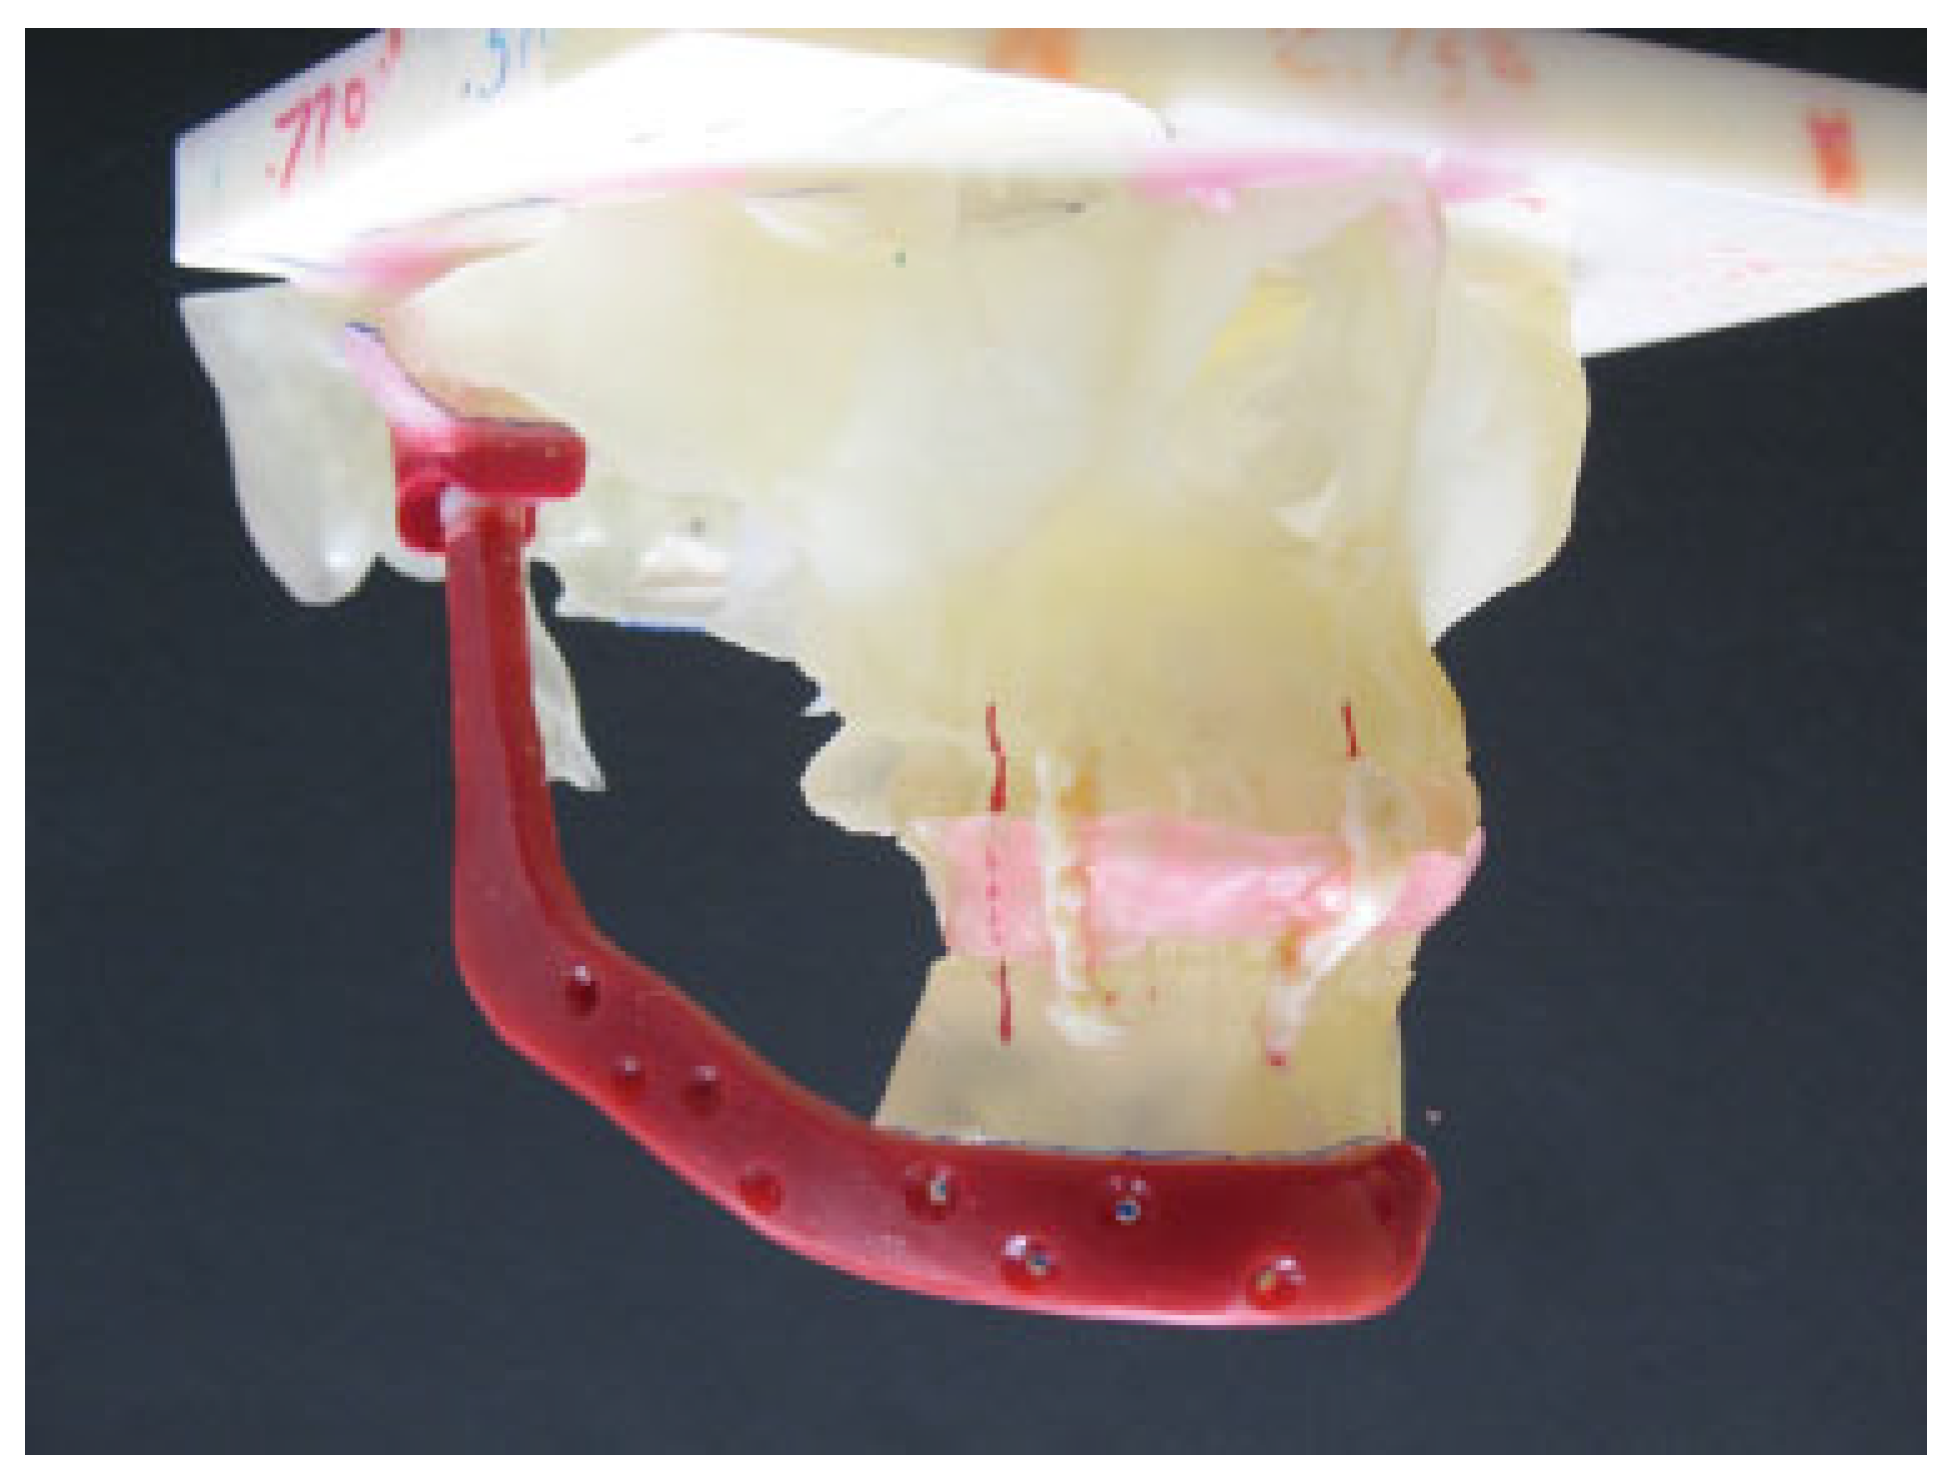

A CT scan with maximum of 1-mm cuts was obtained, which did not reveal any abnormalities in the joint. Free vascularized flap or a custom-made prosthesis was suggested to the patient, and pros and cons with each procedure were explained. Because of the large defect, the desire of the patient to limit scarring on the face, and also the fact that the patient did not express any wish to replace the missing teeth, it was decided to perform reconstruction with an alloplastic total joint prostheses rather than with a vascularized flap. The CT scan was sent to TMJ Concepts technician where a three-dimensional (3D) stereolithographic skull model was created. The left hemimandible was mirrored and an extended custom-made prosthesis was waxed up and fabricated eventually (Figure 5 and Figure 6). A hole was made in the condyle for a vertical suspension suture.

Figure 5. Vax-up of the extended custom-made prosthesis made on a 3D stereolithographic model.